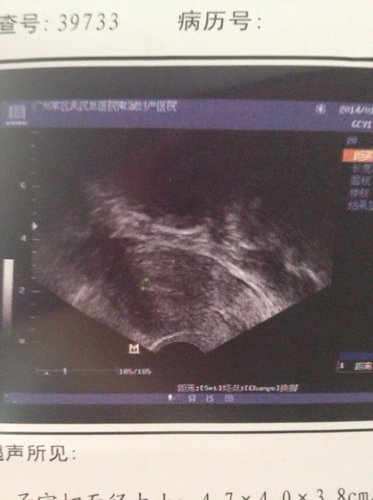

病情分析: 你好:;看你的超生检查结果,显示现在带有节育环,内膜薄,卵巢内有多个卵泡发育,没有发育成熟的,所以可能会影响怀孕的。 指导意见: 如果想要怀孕需要先取出节育环,然后观察三四个月还内膜是否正常,卵巢内的卵泡看是否多个,这是对于怀孕很重要的,注意做激素六项检测看是否多囊卵巢综合征。